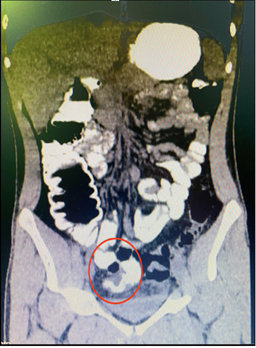

El diagnóstico de abdomen agudo se llevó a cabo mediante el examen físico y estudios complementarios. El hemograma demostró la presencia de neutrofilia. En la totalidad de los pacientes se realizó radiografía de abdomen de pie, observando niveles hidroaéreos de intestino delgado en los casos presentados con síntomas obstructivos. En 6 casos se realizó ecografía abdominal, que evidenció escaso líquido libre en fosa iliaca derecha. Solo en 2 pacientes con sospecha de divertículo de Meckel complicado se solicitó una tomografía abdominal que certificó el diagnóstico. El primero era un paciente de 67 años que consultó por dolor centroabdominal y vómitos de 2 días de evolución, sin respuesta al tratamiento médico. La tomografía evidenció la presencia de un saco diverticular de características inflamatorias dependiente del intestino delgado, asociado a niveles hidroaéreos marcados. El segundo corresponde a un joven de 17 años que consultó por guardia por episodios de hematoquezia de 36 horas de evolución, con repercusión hemodinámica, en el cual la videocolonoscopía no evidenció sangrado colónico. La tomografía mostró un fondo de saco ciego a expensas del intestino delgado con presencia de contraste en su interior (Fig. 2).

Figura 2. Tomografía abdominopelviana que evidencia la presencia de una estructura tubular en fondo de saco ciego con contraste en su interior, compatible con divertículo de Meckel.

En esta serie, solo en dos casos se realizó un diagnóstico preoperatorio de divertículo de Meckel complicado, confirmado mediante tomografía computada con contraste oral que mostró una estructura tubular en fondo de saco ciego a expensas del intestino delgado.